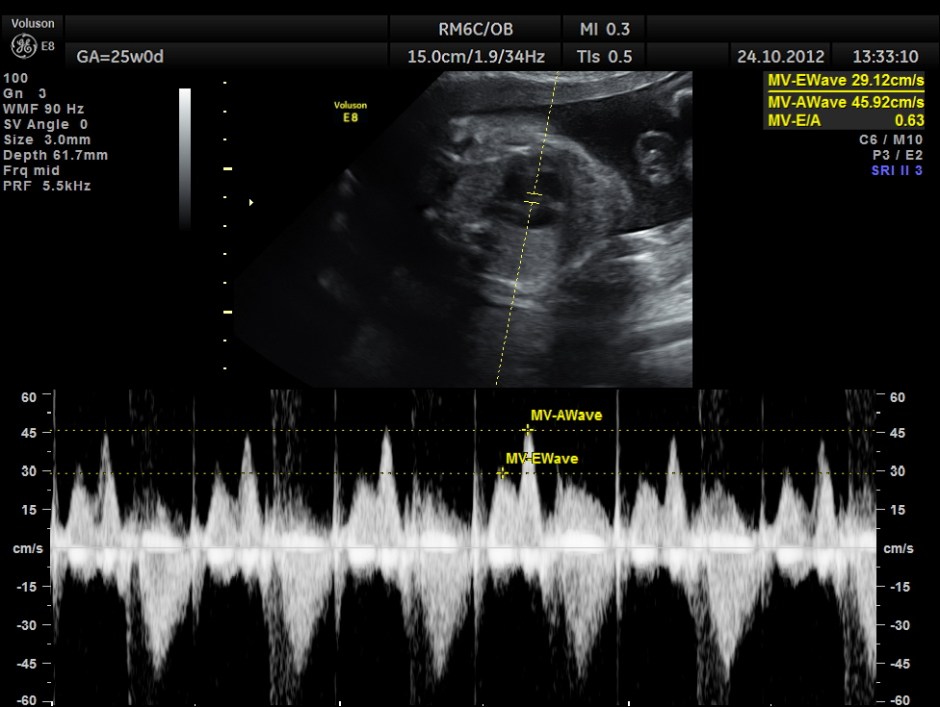

The scan was done around 25 weeks of gestation :

the following are spectral doppler flow across the 4 valves